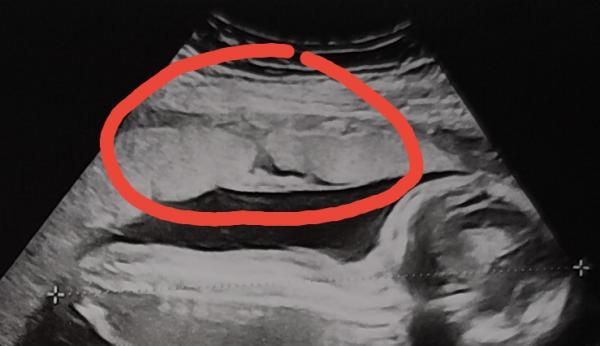

Hallo 😉 Erstmal vorweg, die Ärztin meinte gestern beim Ultraschall, die Plazenta sieht toll aus und ist nicht verkalkt. Als wir dann aber Zuhause die Bilder nochmal alle durchgesehen haben, fiel auf, dass die Plazenta in einem Bereich nicht durchgängig erscheint. Es sieht aus, als würde sich ein Riss quer durch die volle Dicke der Plazenta ziehen. Ich habe es mal im Bild rot eingekreist. Mir ist klar, dass meine Ärztin sicher etwas gesagt hätte, wenn etwas nicht in Ordnung wäre. Aber sie ist auch nur ein Mensch und vielleicht hat sie es übersehen? Die Plazenta hatte sie schon vorher ausreichend angeschaut, vielleicht war die Stelle da aber nicht zu sehen sondern nur lediglich in dem beigefügten Querschnitt? Oder möglicherweise hat sie es gesehen aber nichts gesagt, um uns nicht unnötig zu beunruhigen, weil es vielleicht harmloser ist als es für einen Laien aussieht? Kennt ihr das vielleicht von euren Ultraschallbildern und wisst, was es damit auf sich hat? Ich habe etwas von sogenannten Plazentaseen gelesen, was harmlose mit Blut der Mutter gefüllte Hohlräume sind. Für mich sieht das aber anders aus, weil es eben nicht wie für Gefäße im Ultraschall typisch kreisförmig aussieht, sondern wirklich wie ein Riss. Komisch finde ich generell, dass der an die Gebärmutterwand angrenzende Bereich der Plazenta nicht (weiß) aussieht, wie der Rest der Plazentastruktur, ich hoffe ihr versteht wie ich das meine.. Viele Grüße, Susuba 19+0